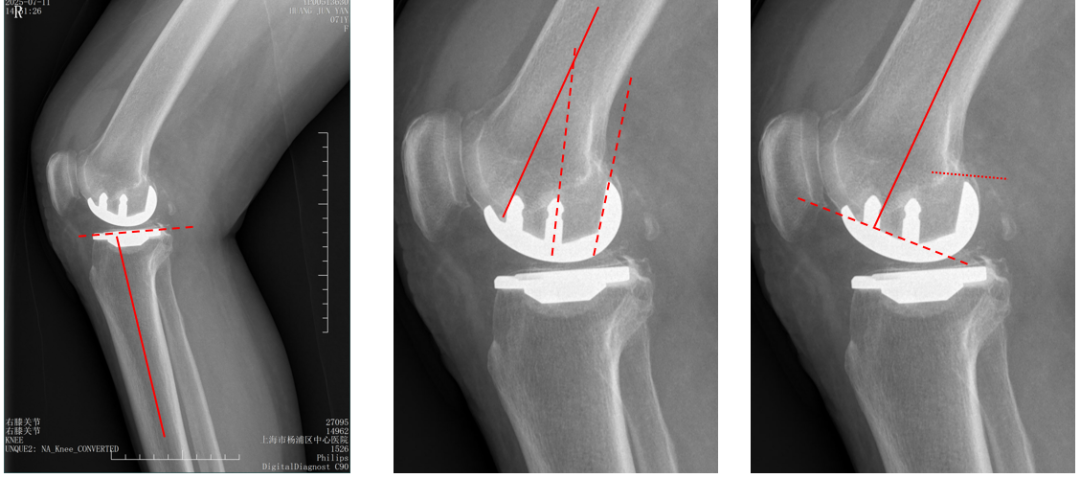

股骨假体过屈(皮质损伤)

侧位股骨假体位置:股骨远端后倾15°截骨,导致后髁115°截骨,后侧皮质损伤。

股骨假体过伸

侧位股骨假体位置:股骨远端前倾10°截骨,导致股骨股骨后髁截骨与股骨髓腔中心轴平行,股骨假体过伸。

股骨后髁过截

外侧股骨髁坏死伴发育不良。

股骨假体过屈

外侧单髁术后股骨后髁过截,股骨假体过屈(45°)。